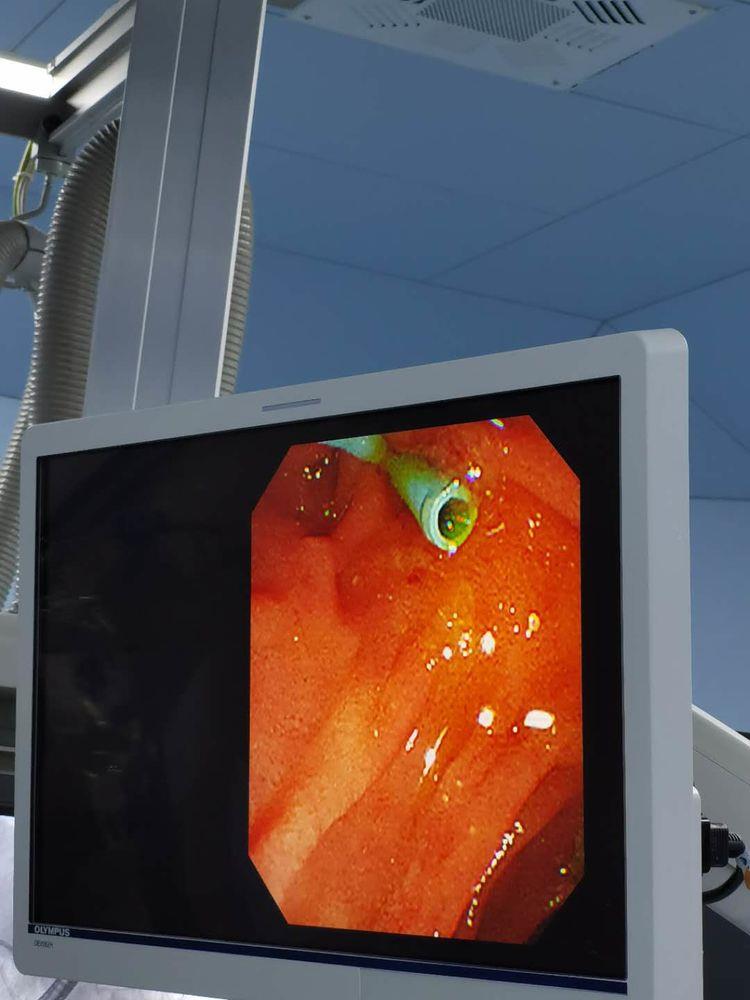

术中:内镜下十二指肠乳头插入导丝